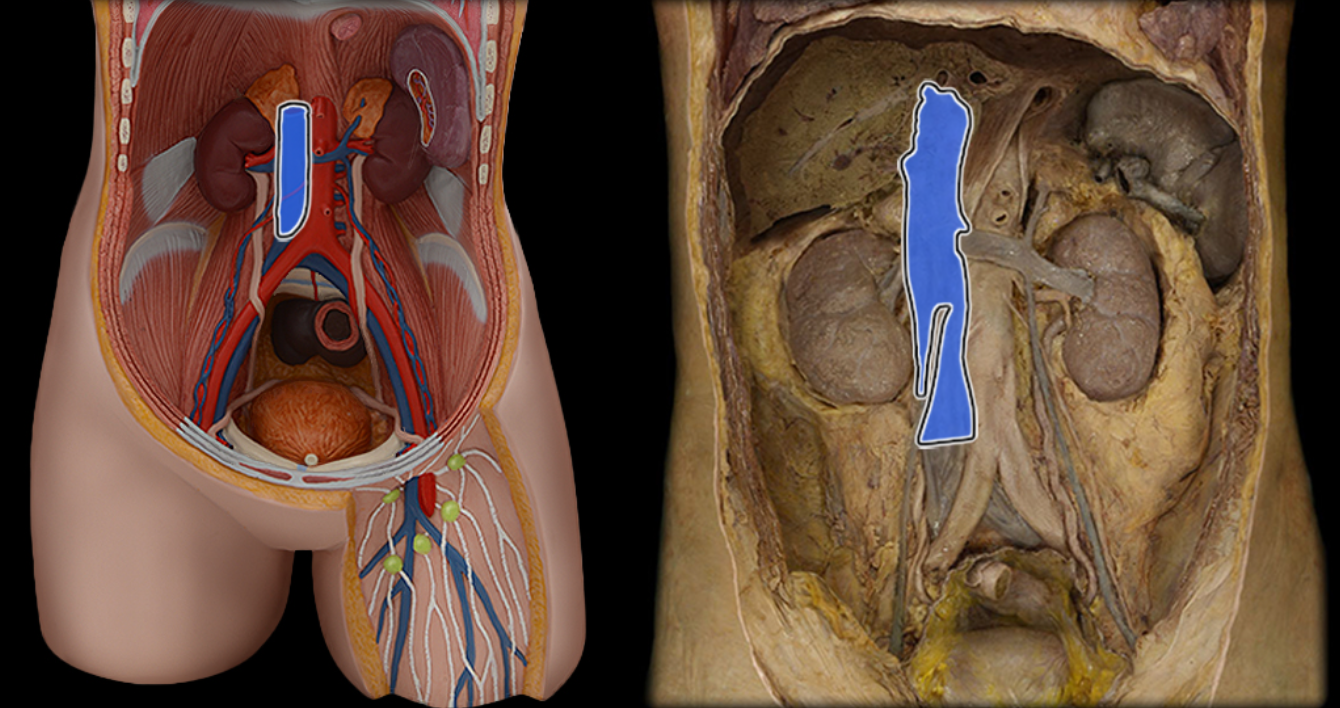

Abdominal aorta

Common iliac a.

Common iliac v.

External iliac a.

External iliac v.

Femoral a.

Femoral v.

Gonadal a.

Gonadal v.

Inferior vena cava

Lumbar a.

Lumbar v.

Renal a.

Renal v.

Superior mesenteric a.